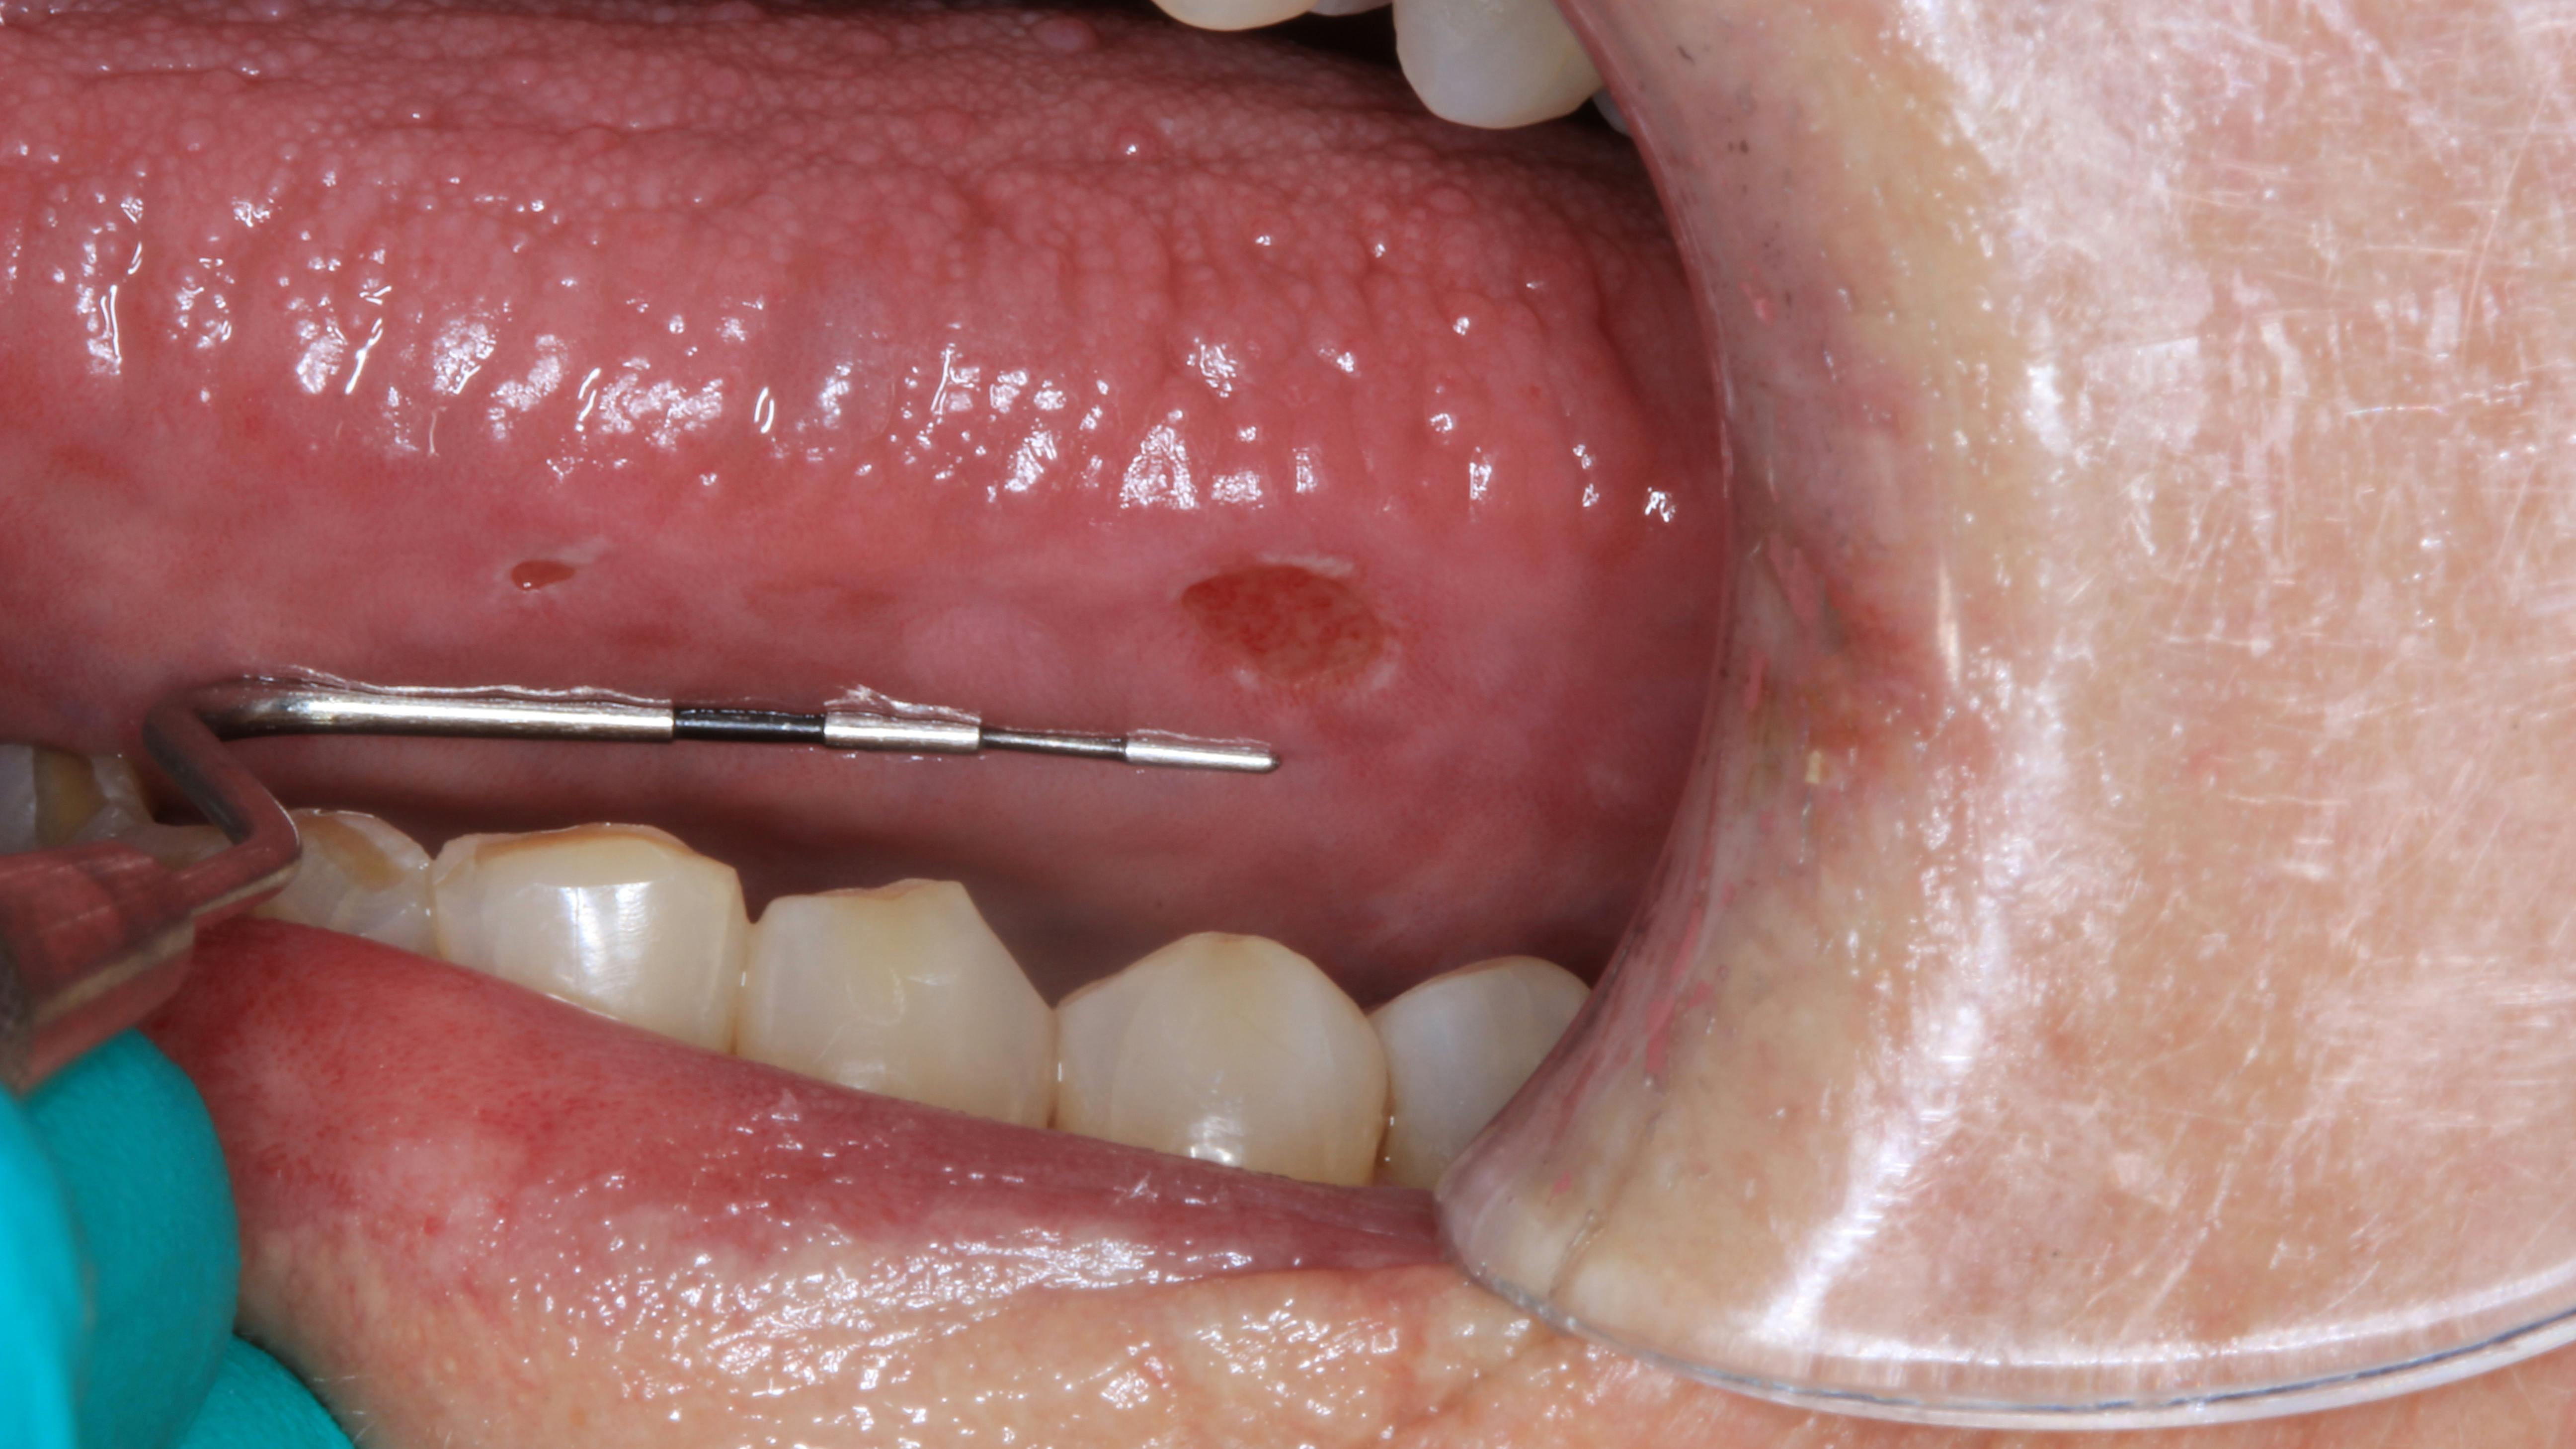

Clinical assessment revealed overall red, inflamed tissue throughout the oral cavity. Most notably present were large, ulcerlike lesions on the right and left lateral borders of the tongue (figures 1 and 2). The edges were well-defined and the red center slightly concave and very tender to palpation. Further, the vestibular tissue, upon the slightest touch, sloughed and hemorrhaged easily. Angular cheilitis was observed, and opening was painful (figure 3).